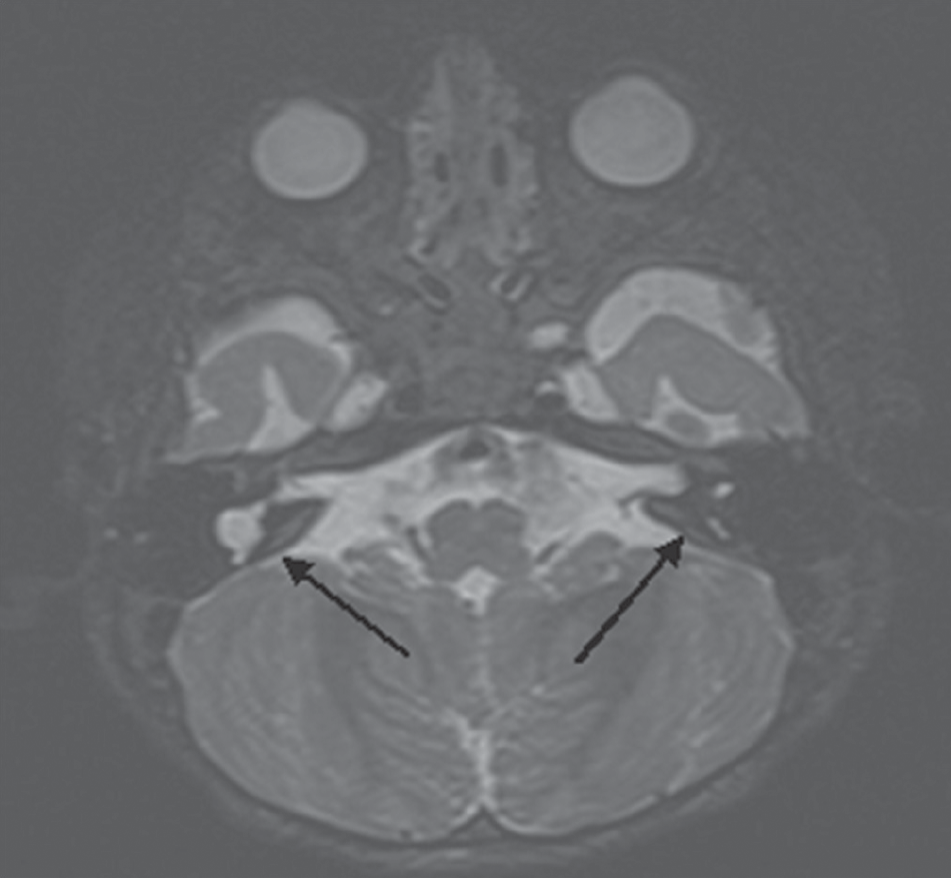

По данным различных авторов, у 20% детей с сенсоневральной тугоухостью или глухотой по результатам компьютерной томографии определяются аномалии строения височных костей. Кохлеарная имплантация при наличии кохлеовестибулярных аномалий сопряжена с рядом трудностей. К ним относятся особенности выполнения кохлеостомии и размещения электрода внутри улитки, риск повреждения лицевого нерва из-за его аномального расположения и его аберрантная стимуляция в послеоперационном периоде, интраоперационная ликворея, что может привести к развитию бактериального менингита в послеоперационном периоде, а также опасность проникновения электрода во внутренний слуховой проход. В данной работе представлен наш способ выполнения кохлеарной имплантации при аномалии развития внутреннего уха – общей полости. Способ расширяет возможности кохлеарной имплантации для восстановления слухового восприятия у пациентов с данной патологией.